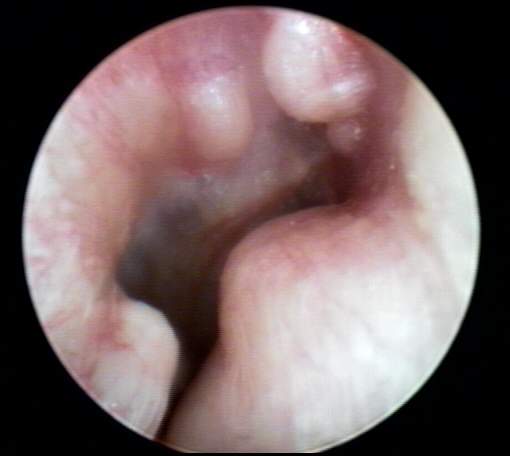

EXTERNAL AUDITORY CANAL

TYMPANIC MEMBRANE / MIDDLE EAR